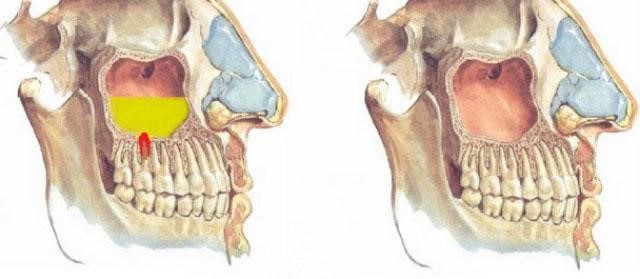

Развитие патологии обусловлено анатомическими особенностями строения гайморовой пазухи, которая прилежит к корням верхних задних зубов. Наиболее часто инфицированные вторые премоляры и первые моляры являются причиной одонтогенного синусита, однако и первые премоляры, вторые и третьи моляры и даже клыки могут привести к развитию данного заболевания.

Диагноз ставится на основании клинических и рентгенологических симптомов, данных анамнеза. Лучше всего провести компьютерную томографию, на которой будет видна степень пневматизации пазух, рентгенологические изменения на верхушках причинных зубов, соотношение их корней с пазухой.

- Риногенный гайморит, как привило, охватывает все стенки пазухи, в то время как воспалительный процесс от зуба приводит к изолированному поражению (нижней, передний или наружной стенки).